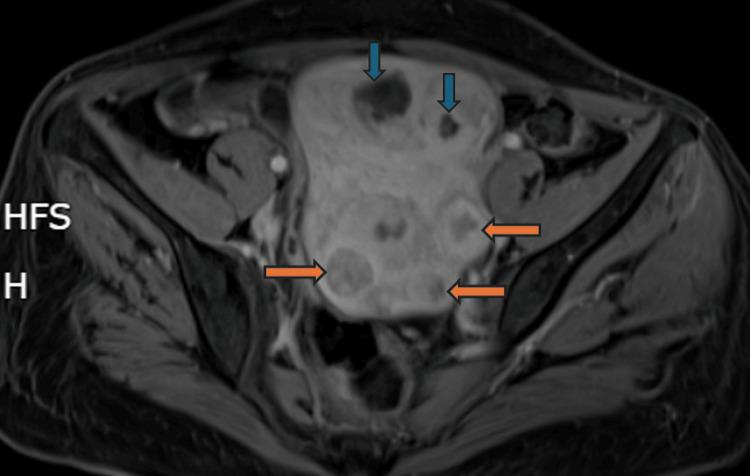

Stiff person syndrome (SPS) is a progressive autoimmune disorder characterized by muscle rigidity, frequent falls, and spasms, affecting primarily women. Recent advances have linked SPS to specific antibodies, such as anti-glutamic acid decarboxylase (GAD)-65, but effective treatments remain elusive. We report the case of a 53-year-old female who developed chronic lower back pain, tingling paresthesias, and progressive rigidity in the lower limbs. Electromyographic examination revealed muscle spasms and co-contractions, along with severe rigidity and reactive spasms upon touch. Imaging studies showed a polymyomatous uterus and no hypermetabolic lesions. She was diagnosed with stiff person syndrome with positive anti-GAD65 autoantibodies. Patient was treated with methylprednisolone, oral corticosteroids, gabapentin, baclofen, alprazolam, immunoglobulins, and rituximab, leading to moderate improvement in her condition. This case report aims to highlight the association between SPS and anti-GAD65 autoantibodies, emphasizing the importance of early diagnosis and comprehensive management.

僵人综合征(SPS)是一种进行性自身免疫性疾病,其特征为肌肉僵硬、频繁跌倒和痉挛,主要影响女性。最近的研究进展将SPS与特定抗体联系起来,如抗谷氨酸脱羧酶(GAD)-65,但有效的治疗方法仍然难以捉摸。我们报告了一例53岁女性病例,该患者出现慢性下背部疼痛、刺痛感觉异常以及下肢进行性僵硬。肌电图检查显示肌肉痉挛和共同收缩,触摸时伴有严重僵硬和反应性痉挛。影像学研究显示子宫多发肌瘤,无高代谢病变。她被诊断为抗GAD65自身抗体阳性的僵人综合征。患者接受了甲泼尼龙、口服糖皮质激素、加巴喷丁、巴氯芬、阿普唑仑、免疫球蛋白和利妥昔单抗治疗,病情有中度改善。本病例报告旨在强调SPS与抗GAD65自身抗体之间的关联,强调早期诊断和综合管理的重要性。